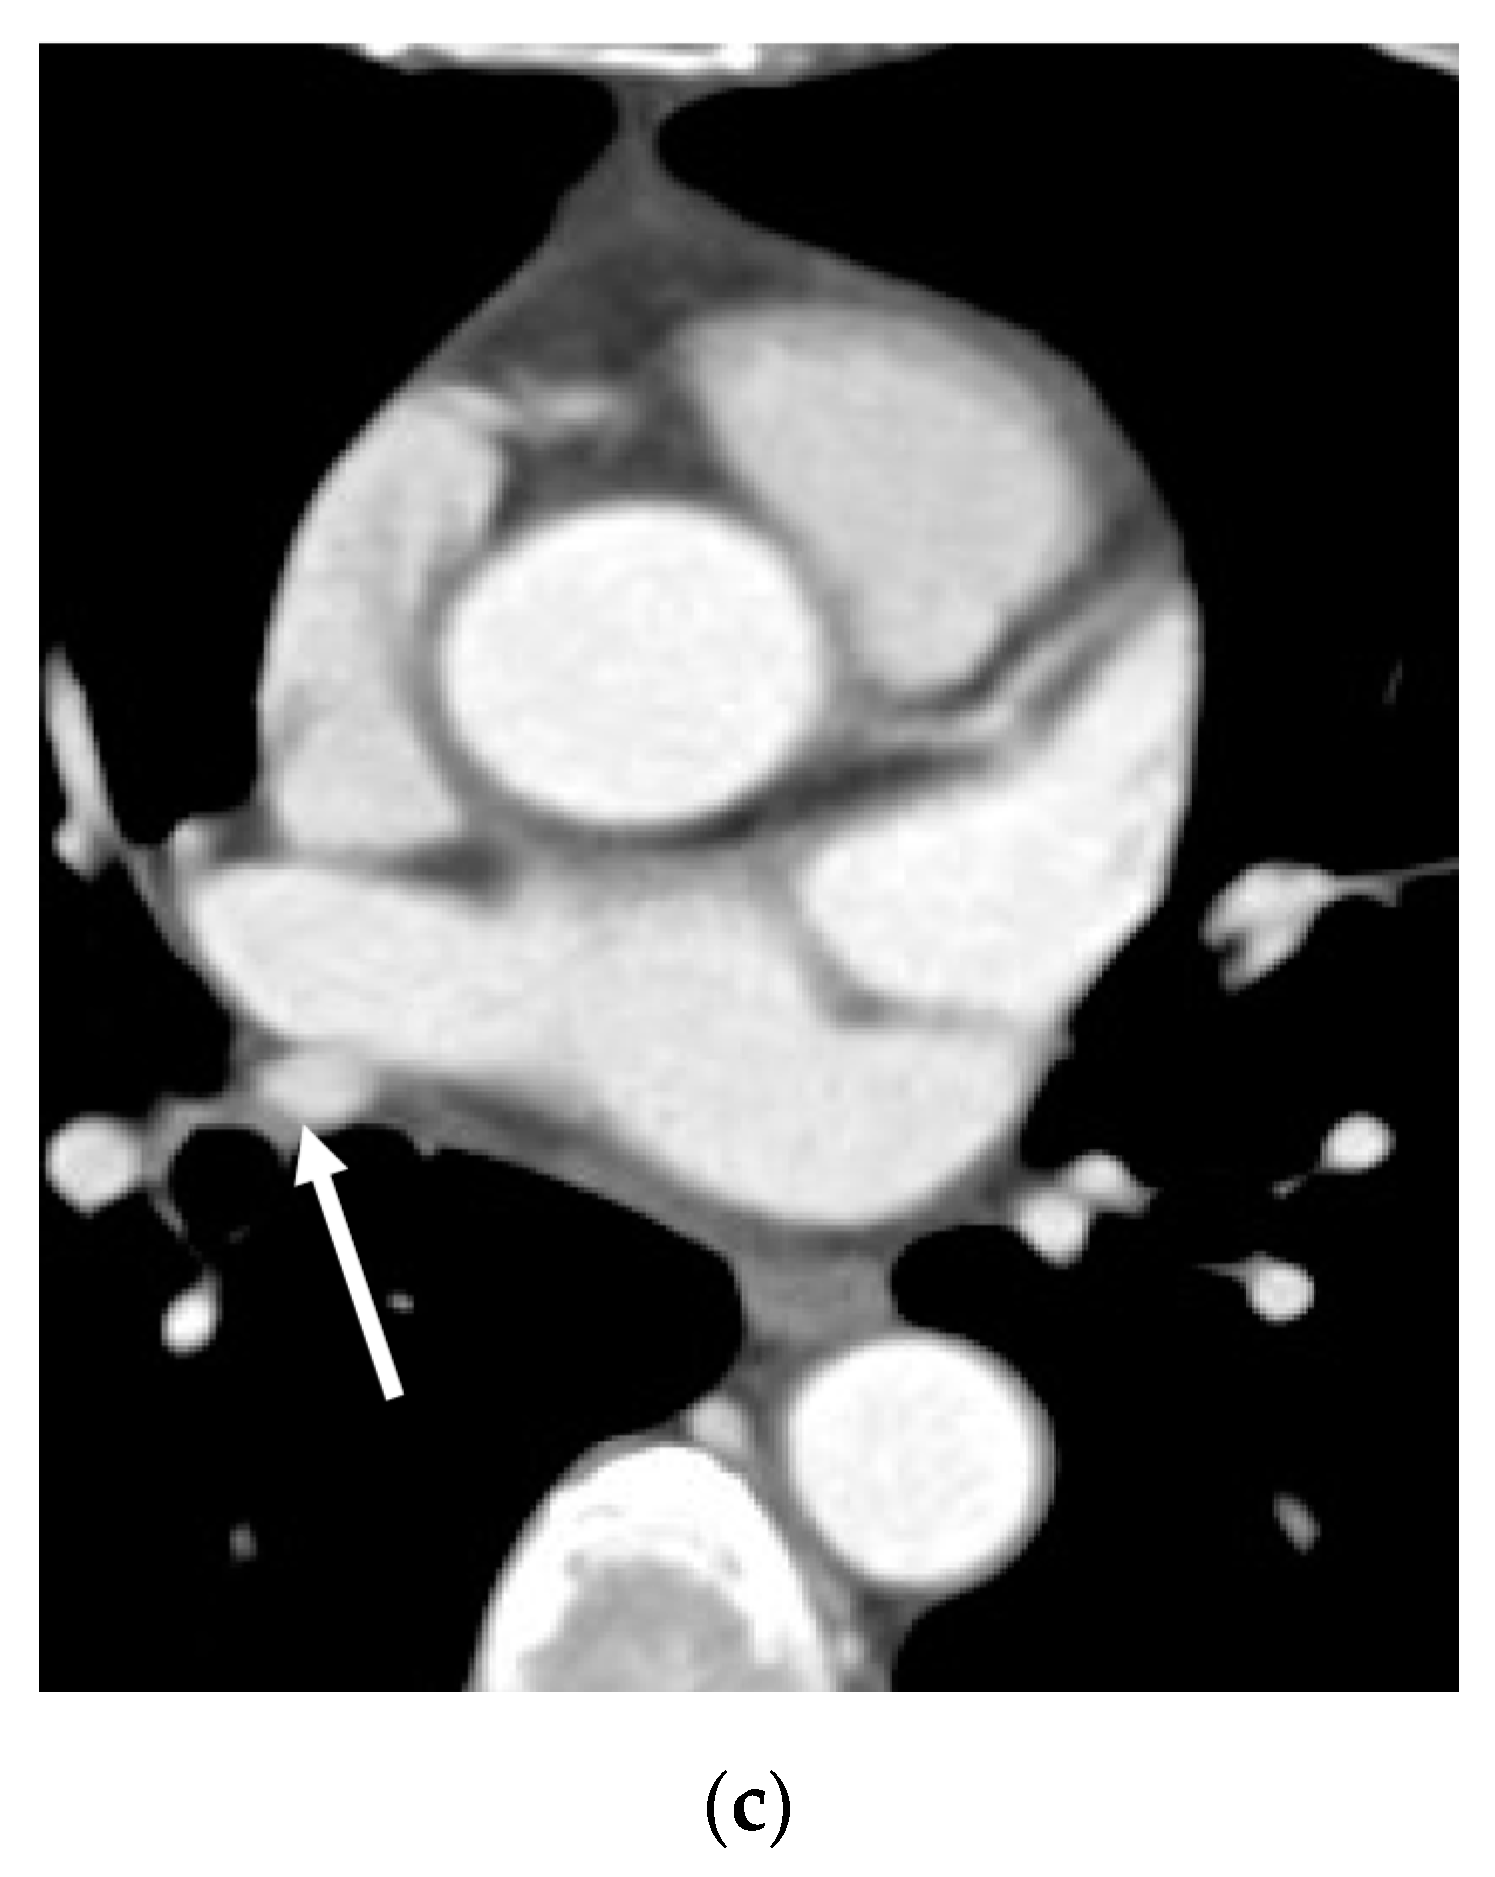

3. Results

3.1. Incidence

3.2. Lobar and Segmental Supply Patternf of the AP

3.3. Diameter of the AP

3.4. Presence of Other Accompanying Variations